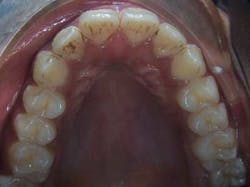

From the beginning, Rachael’s dad wasn’t convinced that his daughter needed orthodontic treatment. After all, her teeth were already relatively straight, as can be seen in the photos below.

Rachael’s dad was reluctant to even schedule a consult appointment, but his dentist insisted that significant improvements could be made to Rachael’s appearance. The fact is that both Rachael’s dad and the dentist were correct in their assessments. In other words, the teeth won’t look much straighter, but Rachael’s appearance would be significantly improved. How could that be?